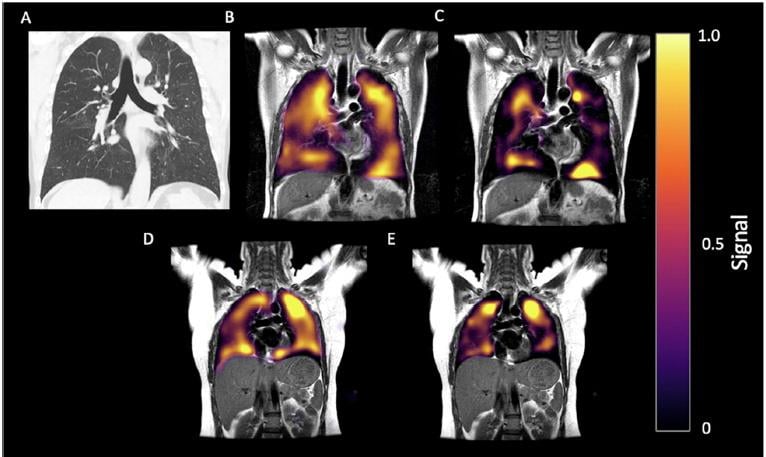

This photo gallery shows the variety of radiological presentations of COVID-19 (SARS-CoV-2) in medical imaging, including computed tomography (CT), radiograph X-rays, ultrasound, echocardiograms and magnetic resonance imaging (MRI). The radiology images show examples of typical COVID pneumonia in the lungs and the numerous complications the virus causes in the body in multiple organs, including the brain, kidneys, heart, abdomen and vascular system.